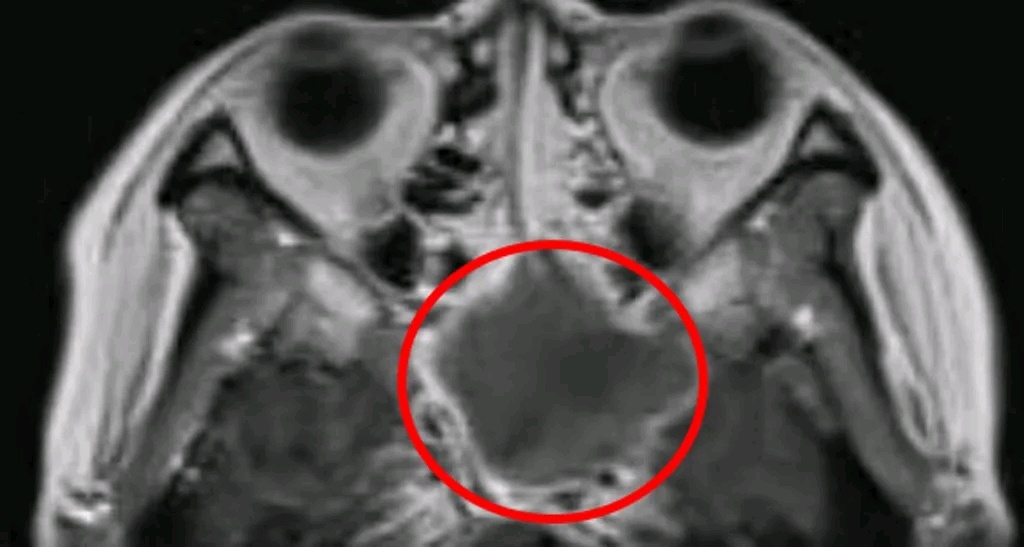

患者鼻窦位置长“霉”。

医生发现,原来陈燕的头痛只是“障眼法”,真正的病因在鼻窦的蝶窦位置。由于该位置发生了真菌感染的炎症,导致出现头痛等一系列症状。